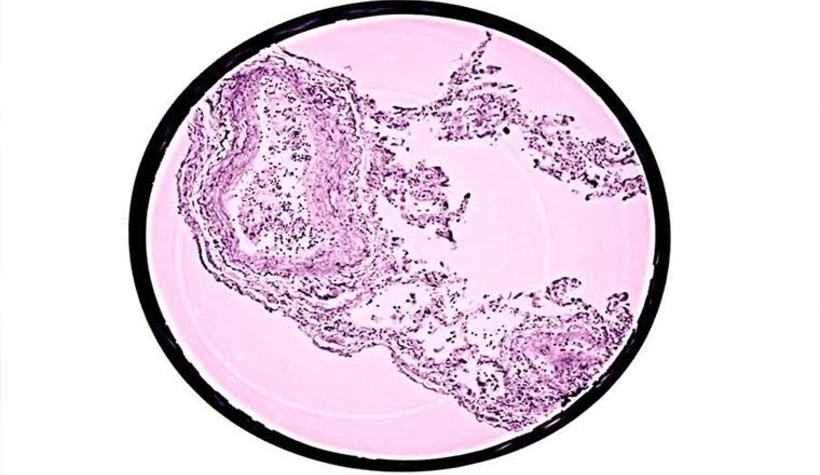

Biyomedikal ve yaşam bilimleri alanında araştırmalara yer veren eLife dergisinde yayımlanan bir çalışmada, koronavirüsün akciğerlerde yayılımı ilk kez üç boyutlu modellendi. Araştırmacılar, özel bir X-ışını mikroskobu tekniği kullanarak koronavirüsün, alveollerin (akciğerdeki küçük hava keselerinin) yapısında ve damar sisteminde ortaya çıkardığı değişiklikleri gözlemlediklediler.

Araştırmacılar, oldukça şiddetli seyreden Covid-19 hastalığında alveollerin duvarlarında biriken ve protein ve ölü hücre topluluklarından oluşan, gaz alışverişini zorlaştıran veya imkansız hale getiren damar sistemi, iltihaplanma, kan pıhtıları ve özellikle de “hiyelin (akciğer) zarında” meydana gelmiş önemli değişiklikleri buldular. Yeni görüntüleme yaklaşımları ile bu değişiklikler ilk defa dokuyu kesmeden, boyamadan ya da dokuya zarar vermeden gerçekleştirildi.

Bu teknikğin küçük kan damarları ve bu damarların dallanmalarını üç boyutta görüntüleyerek iltihaplanma durumunda bölgeye akın eden bağışıklık sistemi hücrelerinin yerini tespit etmek ya da alveollerin duvar kalınlıklarını ölçmek gibi birçok şeyi görüntülememize olanak tanıyacağı duyuruldu.